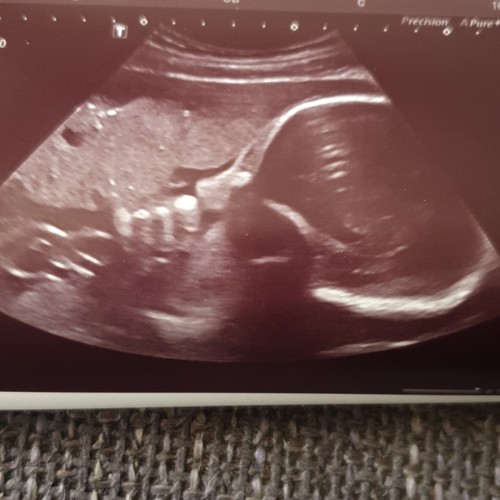

Gebeld en de vk zegt, ik was er niet bij en heb de foto's niet gezien maar als het iets opvallends was dan had je het gehoord en hadden ze het ook aan ons doorgespeeld, daar hebben wij goede contacten mee.(die school die de echo's maakt) ze zei dat het soms wel wat vertekend beeld kan zijn door bepaalde echo technieken o.i.d. Dus daar ga ik dan maar van uit. Ze beweegt in ieder geval flink en groeit goed... haha